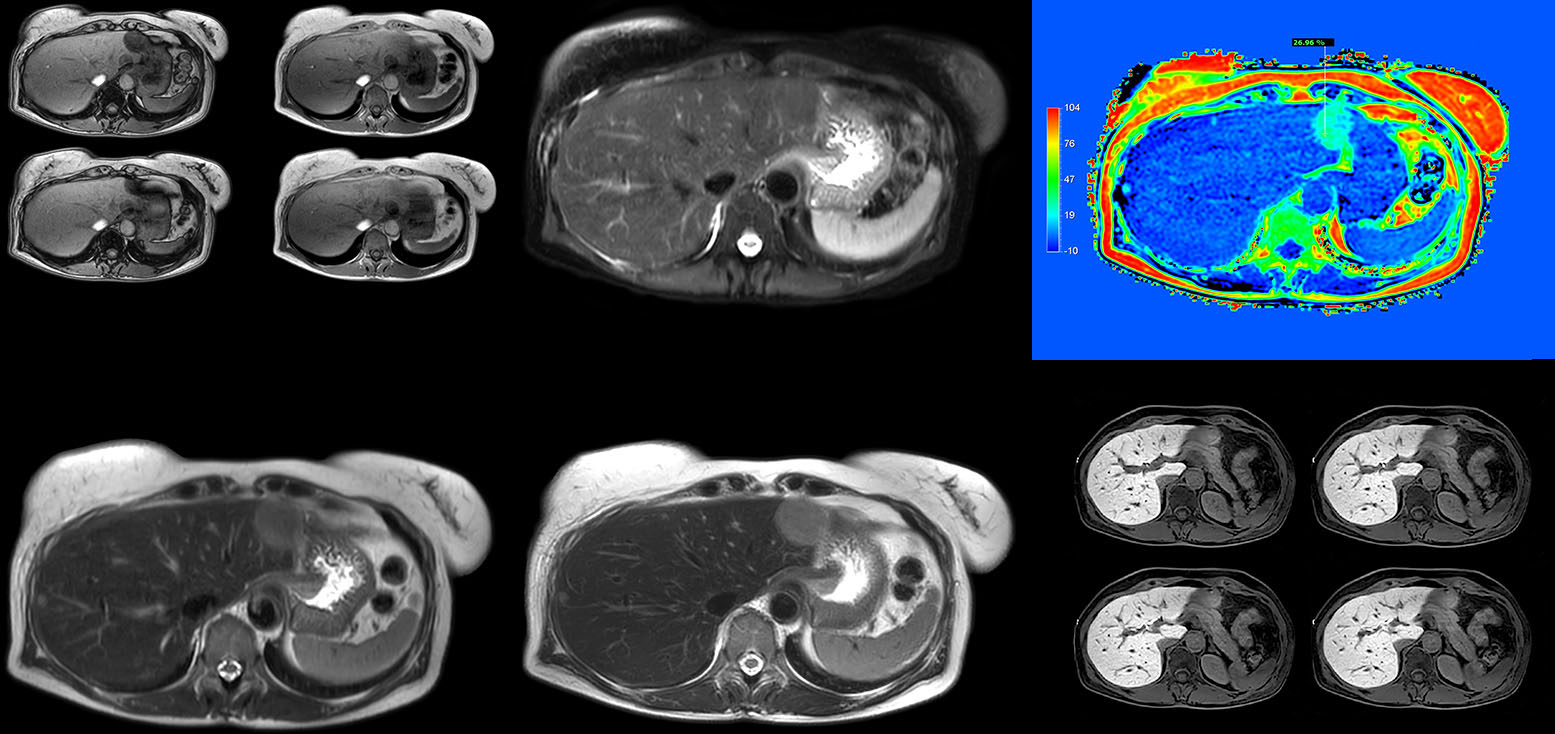

Dr. Kukuk’s liver exam begins with T2-weighted imaging, single shot and with fat suppression. “We always perform diffusion weighted imaging (DWI) with four b-values (0, 50, 250, 800) for lesion characterization, for monitoring after therapies, and for visualization of small lesions. Before giving contrast we routinely use the mDIXON Quant fat quantification sequence. Then we use dynamic e-THRIVE with an in-plane spatial resolution of 1.5 mm and high temporal resolution in just four breathholds of 13.1 seconds.”

“Contrast enhancement is important to help us characterize lesions, for follow up in oncology patients and to inform clinicians when deciding on possible changes in the therapeutic regimen,” Dr. Kukuk explains. “Because we use liver-specific contrast agents we can obtain the T2-weighted images after the dynamic, to bridge the waiting time needed with these contrast agents. Just before the patient leaves the scanner we acquire another e-THRIVE in the axial plane and one or two coronals.”

Robust motion correction and high spatial resolution with MultiVane XD

“Using MultiVane XD motion correction, we are now able to acquire high spatial resolution T2-weighted images without seeing relevant motion,” says Dr. Kukuk. “It’s a great technique to obtain high spatial resolution images of the pancreas or the liver, as well as the surrounding organs and tissues. MultiVane XD can be combined with dS SENSE parallel imaging, allowing us to reduce specific absorption rates (SAR), acquire high spatial resolution in short acquisition times, and at the same time reduce artifacts caused by motion in adjacent tissues and organs.”

“In comparison to single shot T2-weighted TSE, this approach with MultiVane XD motion suppression provides higher spatial resolution. In addition, it is especially valuable in patients who cannot hold their breath or have some disabilities. My impression is that this sequence has the potential to substitute for, or even replace, the T2-weighted single shot sequence in our liver exams, because of good and consistent delineation of small lesions.”

“We have performed a study comparing mDIXON Quant fat percentages with results from histopathology. The correlation with different histologic methods was very good and also the correlation with MR spectroscopy was far above 0.9 – a nearly perfect correlation,” says Dr. Kukuk.

Non-invasive liver fat quantification in a breathhold with mDIXON Quant

“Fatty liver disease is a common condition. Studies found a prevalence of non-alcoholic fatty liver disease in up to 44% in the general European population [1]. Liver fat cannot be quantified by ultrasound or CT, so biopsy has been the way to quantify fatty liver disease so far,” says Dr. Kukuk. “mDIXON Quant now allows non-invasive quantification of liver fat, which is valuable for both diagnosis and follow-up during dietary changes or therapy, for instance in hepatitis C.”

“The mDIXON Quant fat fraction maps provide quantitative information and also anatomical detail. The sequence is fast, usually taking about 16 seconds, which is just a breath hold for most patients. It definitely improves our efficiency.”